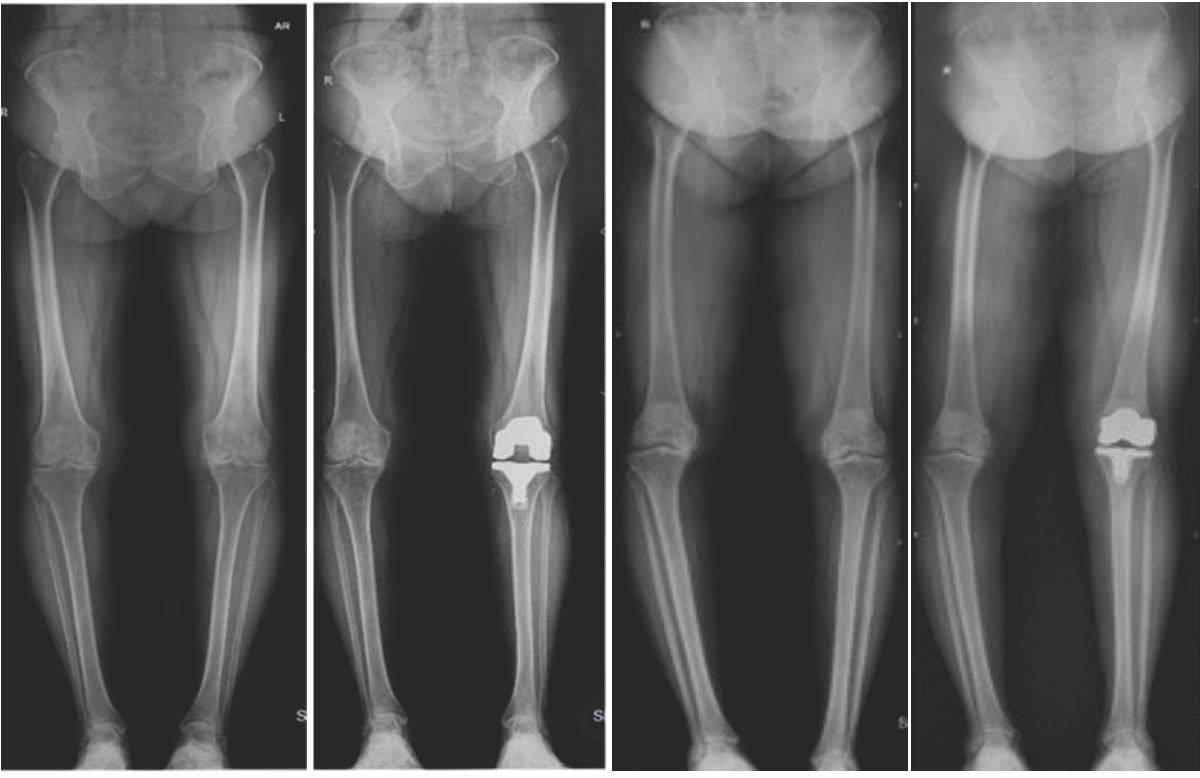

Comparing the pre-operative and post-operative alignment of the lower limb (Fig. 2), there was a decrease in varus measurement before and after TKA and it was statistically significant. In post-operative varus, ≤3° alignment was achieved in 97% (n – 69 knees) and outliers were 3% (n-2 knees). Hence, the neutral alignment was achieved in more number of patients.

Figure 2: Pre op and post op long leg weight-bearing radiological images of study subjects.